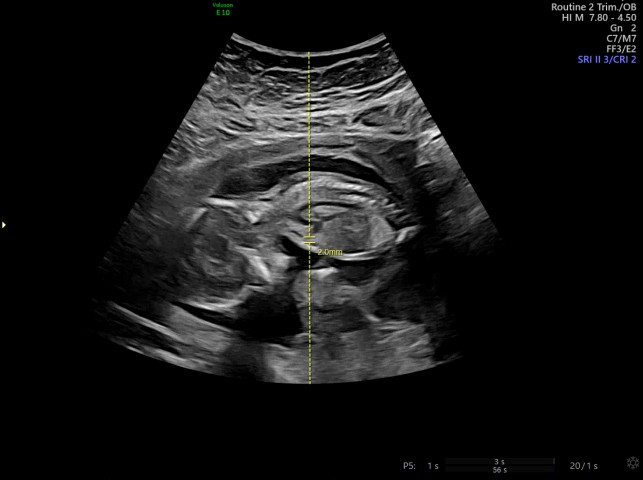

[20주 5일] 정밀초음파 확인 및 얼굴 확인

이번달은 좀 늦게 진료보자하셔서 지난 진료보다 5주정도 뒤에 보았다! 임신전보다는 몸무게가 늘지 않았지...